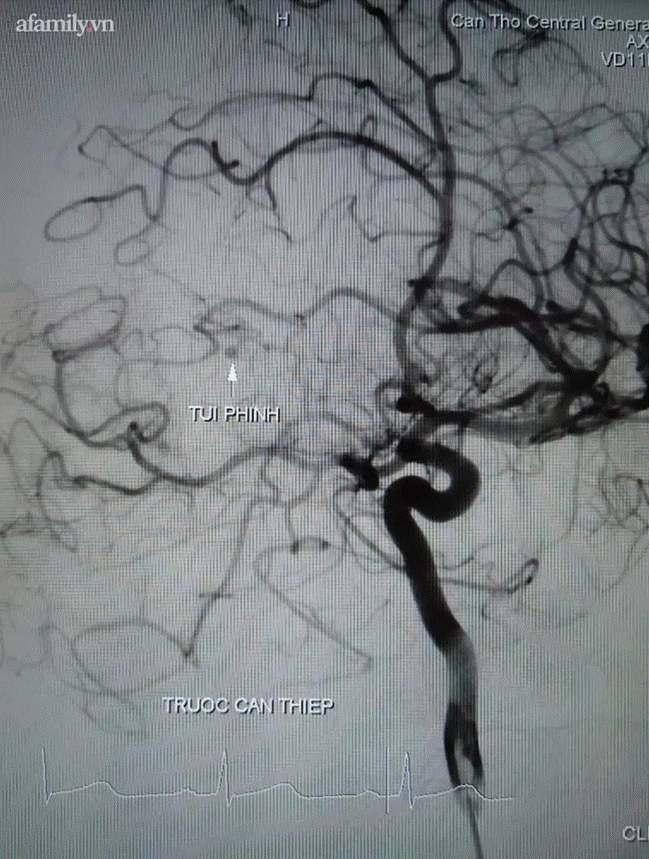

Túi phình của chàng trai 27 tuổi trước can thiệp.

Khi tình trạng bệnh cho phép di chuyển, bệnh nhân đã được chụp cắt lớp mạch máu não để tìm nguyên nhân xuất huyết não.

Tuy nhiên chỉ thấy được hình ảnh xuất huyết lan tỏa ở vùng chẩm trái và chảy vào hệ thống não thất.

Sau khi hội chẩn, các bác sĩ đã quyết định thực hiện chụp mạch máu kỹ thuật số xóa nền với 2 ekip bác sĩ khoa Ngoại Thần kinh và khoa Phẫu thuật – Gây mê hồi sức.

Kết quả chụp cho thấy có búi dị dạng động tĩnh mạch não vị trí gần não thất bên ở bên trái nên bệnh nhân được tiến hành nút dị dạng và bảo toàn các nhánh mạch máu lành.